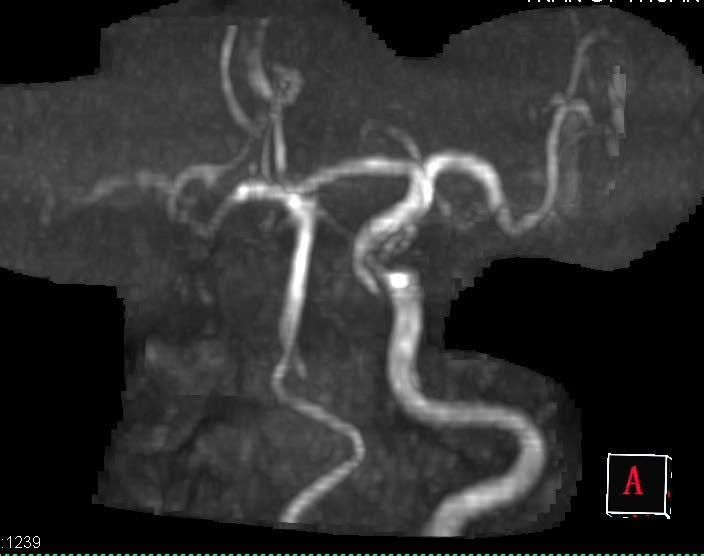

🍀Kết quả MRI ghi nhận:

🔷Hình ảnh ổ nhồi máu mạn tính hồi trước trung tâm phải

🔷Ổ tổn thương cũ bán cầu tiểu não trái

🔷Teo não tuổi già

🔷Tắc hoàn toàn động mạch cảnh trong phải, kèm theo động mạch não giữa phải tín hiệu kém